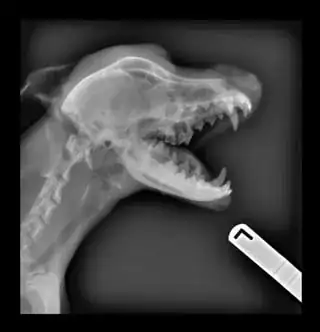

A medical x-ray of your skeleton actually shows something totally different from a diffraction image like the one above. The bones are thick enough to absorb the x-rays that pass through them --- or at least to scatter all of the x-rays away from the forward beam direction. What's recorded on the x-ray film are dark places where x-rays do hit, and brighter places where x-rays don't hit: the bright places on the x-ray film are the shadows of the dense parts of the subject. (Photographers call this a negative image.) Any x-rays diffracted away from the bones are most likely to diffract into a region of the film that's directly exposed to the primary x-ray beam, where they'll be overwhelmed.

The fact that bone is white, and the shadows on x-ray negatives are white, is just a concidence; those left-right markers aren't really white, but they cast a shadow just the same.